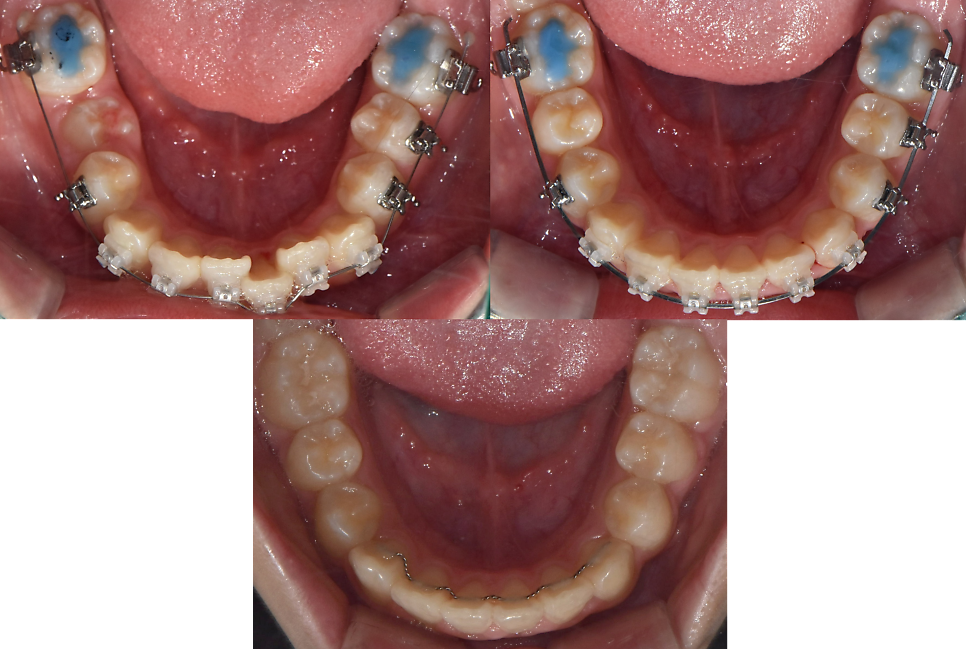

24.02.22 (치료 시작) / 24.05.17 (치료 중) / 24.06.26 (치료 후) – 10y 최OO님

처음 교정치료를 위한 장치를 부착하고

교정치료를 완료할때까지

어느정도의 기간이 소요되었을까요?

앞니삐뚤한 초등학생 부분교정의 경우

삐둘한 정도에 따라

그리고 발치 여부에 따라

소요되는 기간은 달라지게 됩니다.

하지만 오늘 소개해드린 학생의 경우

발치 없이 그리고 유치가 빠진 후 남는 공간을 이용했던

앞니부분교정의 경우로

4개월의 시간이 소요되었습니다.

처음 장치를 부착하고 부터 교정치료가 완료된 후

아래 앞니 안쪽에 유지장치까지 부착하고 촬영한 사진입니다.

4개월 정도의 빠른기간,

그리고 눈에 띄게 바르게 배열된 모습으로

학생 스스로도 정말 좋아했습니다.